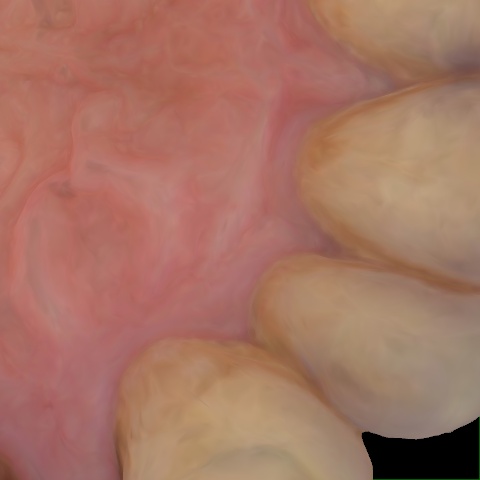

Annotated as "Good"